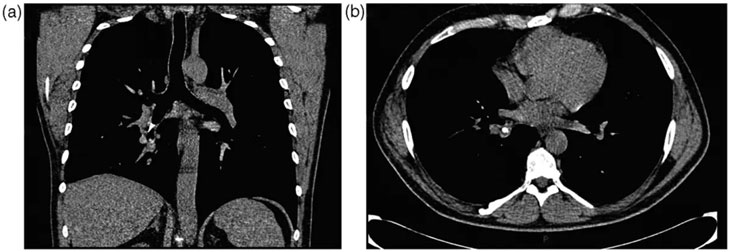

Hospitalisé pour des infections pulmonaires répétées, l’homme âgé d’une quarantaine d’années avait bénéficié de plusieurs interventions visant à drainer le liquide s’accumulant dans ses voies respiratoires. Des examens complémentaires, notamment un scanner, ont révélé la présence d’une masse à la forme étrange à la base de son poumon droit.

Alors qu’ils pensaient initialement avoir affaire à une sécrétion calcifiée, les médecins ont découvert avec étonnement qu’il s’agissait en réalité d’un cône de signalisation miniature. Interrogé à ce sujet, le patient s’est souvenu avoir avalé le jouet lorsqu’il n’avait que 6 ans.